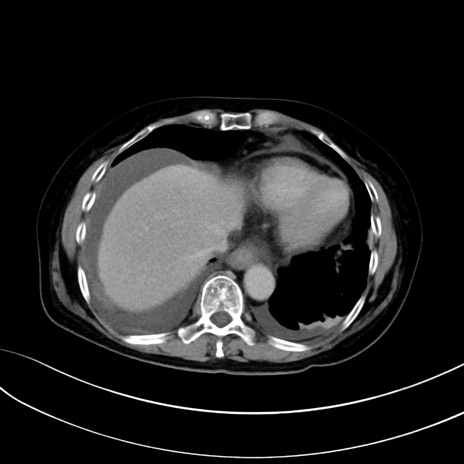

症例13 CT(横断像)1日半後